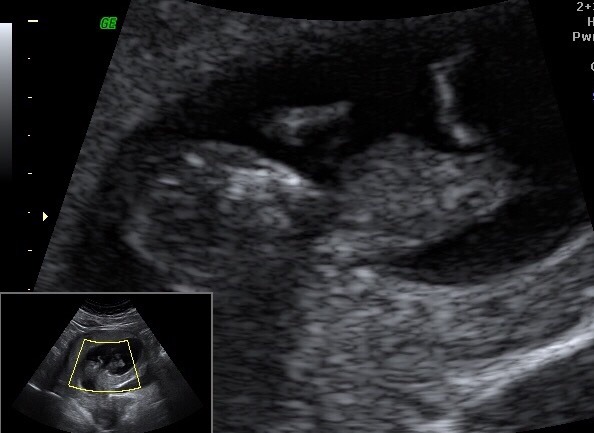

It's a BABY! All looking good, limbs present and correct, normal nuchal fold measurements, strong heart beat and measuring 6 days older so I'm 12 weeks tomorrow. I'm suffering with really bad zits at the moment. Anyone got any advice about getting shot of them?

Pickle great scan photo, glad it all went well. No clue about the zits though, I seem to be keeping fairly clear.

pickle a real baby! I've been saying how odd it is that at 7 weeks we had a blob, and now in 2 weeks we'll see a picture of a real baby! How many pictures do you get?

Yay pickle!!! It's a baby! So glad all went well, I'll be the first to hazard a guess - I think BOY! Are you finding out?

pickle that's a great shot! So exciting.